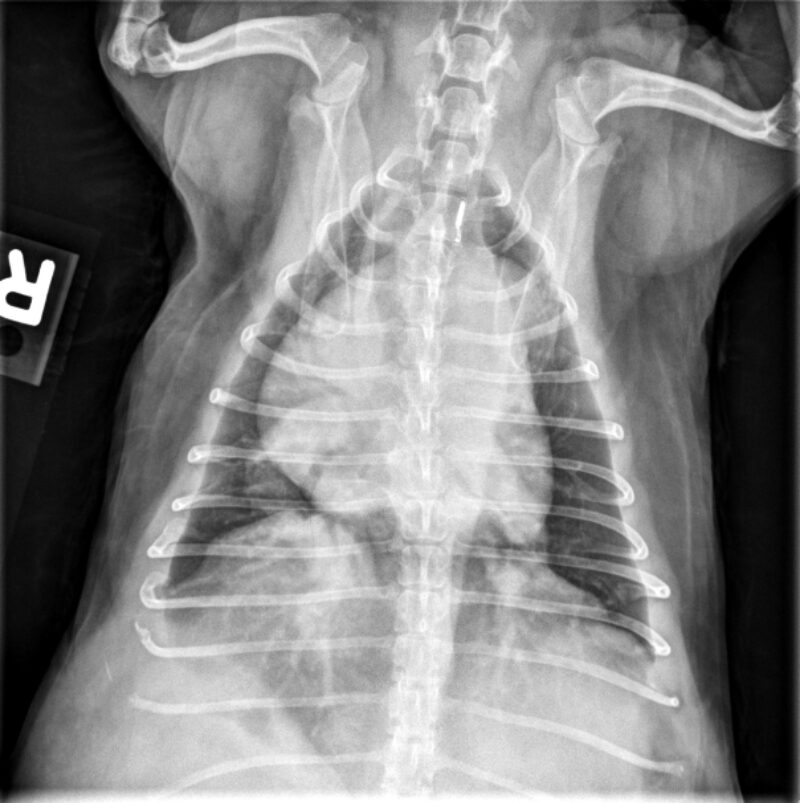

anbei übersenden wir Ihnen die Röntgenaufnahmen unserer Patientin „Valentine“. Es handelt sich um eine 10-jährige, weiblich kastrierte Französische Bulldogge, die in unserer Praxis aufgrund eines seit längerer Zeit bestehenden, chronischen Hustens vorgestellt wurde. Wir würden uns sehr über Ihre Einschätzung der vorliegenden Röntgenbilder freuen: Welche Befunde lassen sich erkennen und welche differenzialdiagnostischen Überlegungen ergeben sich aus Ihrer Sicht?

Dr. Anna Adrian, MS, DACVR, antwortet: Vielen Dank für die Zusendung dieses interessanten Falles. Es liegen eine links- und rechtslaterale sowie eine ventrodorsale Thoraxaufnahme vor. In allen drei Projektionen zeigt sich eine ausgeprägte rechtsseitige Kardiomegalie, die mit einer dorsalen Verlagerung der Trachea sowie einem vermehrten Kontakt des Herzens zum Sternum einhergeht (Bild 1, dunkelblaue Pfeilköpfe). In der ventrodorsalen Projektion imponiert die Rechtsherzvergrößerung als typische „reverse D-Form“ (Bild 2, dunkelblaue Pfeile). Zusätzlich fällt in dieser Ansicht auf Höhe der 2-Uhr-Position eine Vorwölbung auf, die einer Dilatation des Truncus pulmonalis entspricht (Bild 2, dunkelblauer Kreis).

Die kaudalen lobären Pulmonalarterien sind hochgradig erweitert, überschreiten deutlich die Breite der 9. Rippe und zeigen einen geschlängelten Verlauf (Bild 1 und 2, hellblaue Pfeile). Zur Erinnerung Venen liegen in der VD-Aufnahme zentral und in der lateralen Aufnahme ventral, wohingegen Arterien lateral und dorsal gelegen sind. Die Vena cava caudalis erscheint geringgradig dilatiert. Das Lungenparenchym weist insgesamt ein leicht- bis mittelgradig ausgeprägtes bronchointerstitielles Muster auf. Im kranialen Abdomen ist eine kraniale abdominale Organomegalie erkennbar, sowie geringgradige Heterogenität des abdominalen Fettgewebes (Bild 1, hellblau gestricheltes Rechteck). Dieser Befund ist vereinbar mit einer Splenomegalie +/- Hepatomegalie und geringgradiger Aszites. Die übrigen abdominalen Strukturen erscheinen unauffällig.

Zusammenfassend liegen eine ausgeprägte rechtsseitige Kardiomegalie sowie eine deutliche Erweiterung der Pulmonalarterien vor. Die Befundkonstellation spricht für eine pulmonale Hypertension in Kombination mit einer Kardiomyopathie, möglicherweise sekundär infolge einer Herzwurmerkrankung oder eines idiopathischen Cor pulmonale. Zur weiterführenden Abklärung wird eine echokardiographische Untersuchung empfohlen. Das bronchointerstitielle Lungenmuster kann altersphysiologisch bedingt sein, differentialdiagnostisch sind jedoch auch eosinophile Infiltrate im Rahmen einer parasitär bedingten Hypersensitivitätsreaktion in Betracht zu ziehen. Die Dilatation der Vena cava caudalis kann einerseits ein Normvariant darstellen, andererseits im Kontext der Rechtsherzvergrößerung auf eine Rechtsherzinsuffizienz oder ein Vena-cava-Syndrom bei hoher parasitärer Last hinweisen.